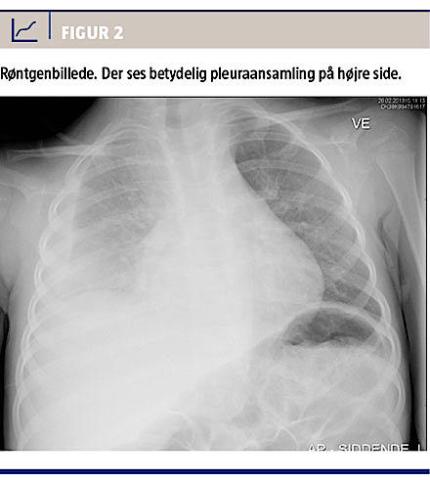

Den nye antibiotikastrategi ændrede ikke pigens tilstand de næste to dage. Hun forblev højfebril 39,5°C. Hun saturerede 94%, CRP-koncentrationen var 124 mg/l, og koncentrationen af de neutrofile granulocytter faldt til 19,6 × 109/l. Stetoskopisk hørtes ophævet luftskifte på højre lunge. Et røntgenbillede (Figur 2) viste betydelig pleuraansamling på højre side.